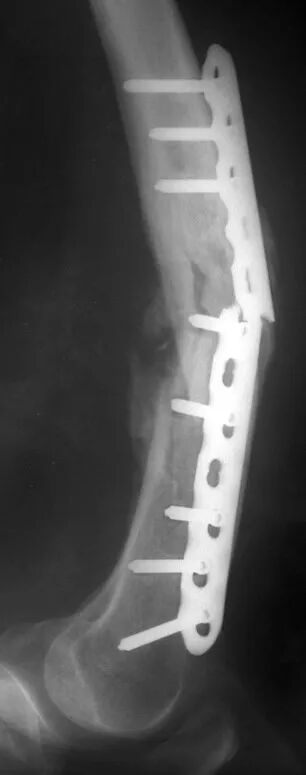

某粉碎性骨折:

使用LCP作为桥接板固定

再经过LCP板向某一碎骨片

打一枚拉力螺钉。

加压与桥接绝对不能混用!

-接骨板未塑形

•  非加压

•  非桥接

-这种“内固定支架”的后果

•  应力集中

•  内固定断裂!

术后

术后10周